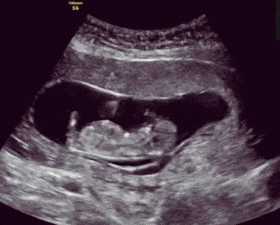

怀孕期间,总有那么几个瞬间让妈妈难以忘怀,一个是第一次听到胎心跳动的声音,一个是胎儿第一次胎动。还记得我第一次听到女儿胎心砰砰跳动的声音时,我的眼泪就流了下来。

胎动,顾名思义就是胎儿在妈妈子宫里活动,比如伸手、蹬腿、翻身、打嗝等,触碰激烈时,妈妈就会有所感觉。一般而言,大多数的孕妇在孕4月开始感受到第一次胎动。